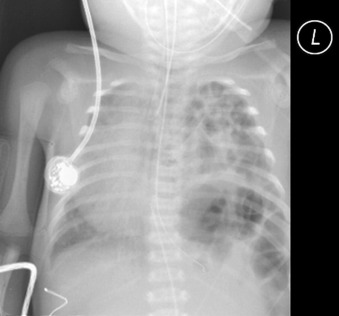

Figure 20-6

In this chest radiograph from an infant, the heart is displaced to the right side, not the apex. The position of the gastric air bubble is ambiguous. The responsible lesion is a large left-sided diaphragmatic hernia, with the stomach and bowel moved into the left chest, displacing the otherwise normal heart and rendering the gastric air bubble obscure.